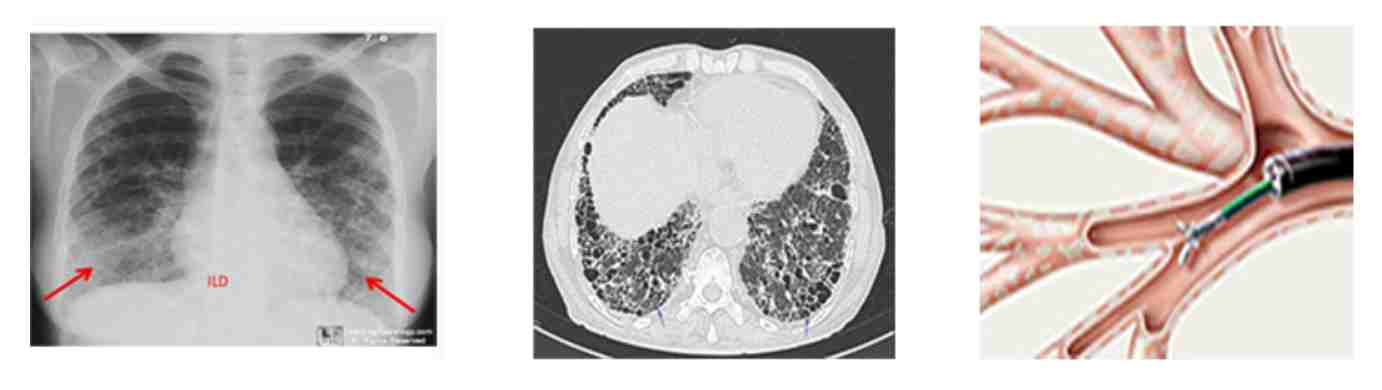

1. Chest X-ray showing reticulo-nodular opacity

2. HRCT chest showing ground glass opacity

3. HRCT Chest showing honeycombing